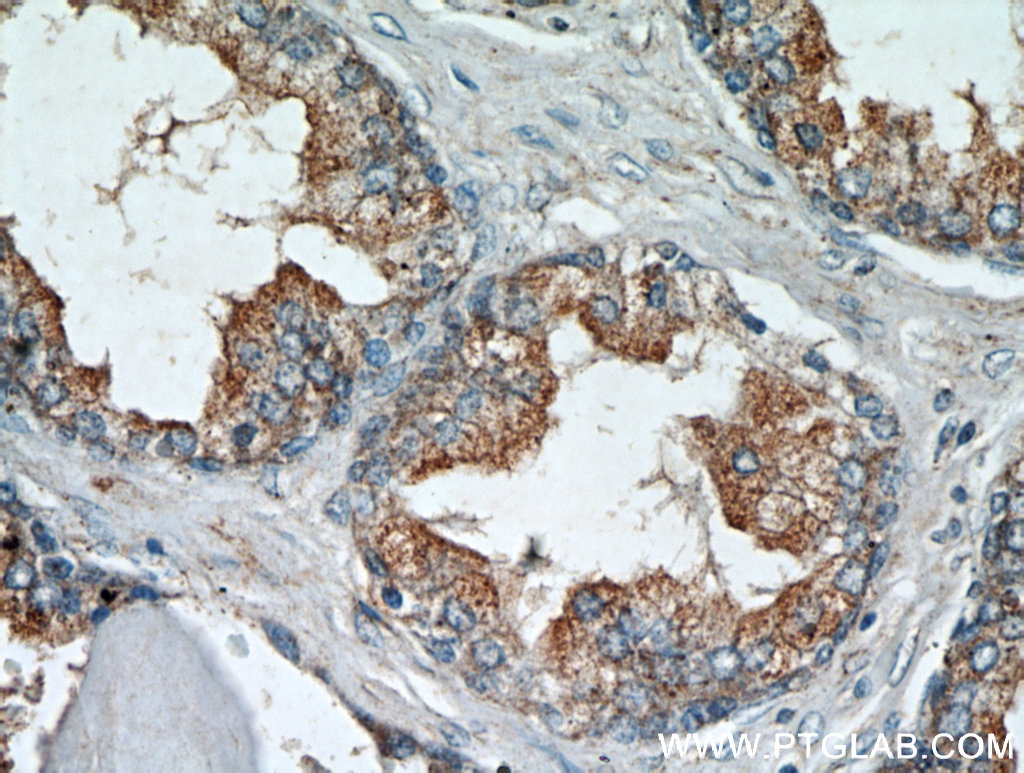

| Positive IHC detected in | human prostate hyperplasia tissue, human heart tissue | ||

| Recommended dilution | WB : 1:500-1:5000 IP : 1:200-1:2000 IHC : 1:50-1:200 IF : 1:10-1:100 |